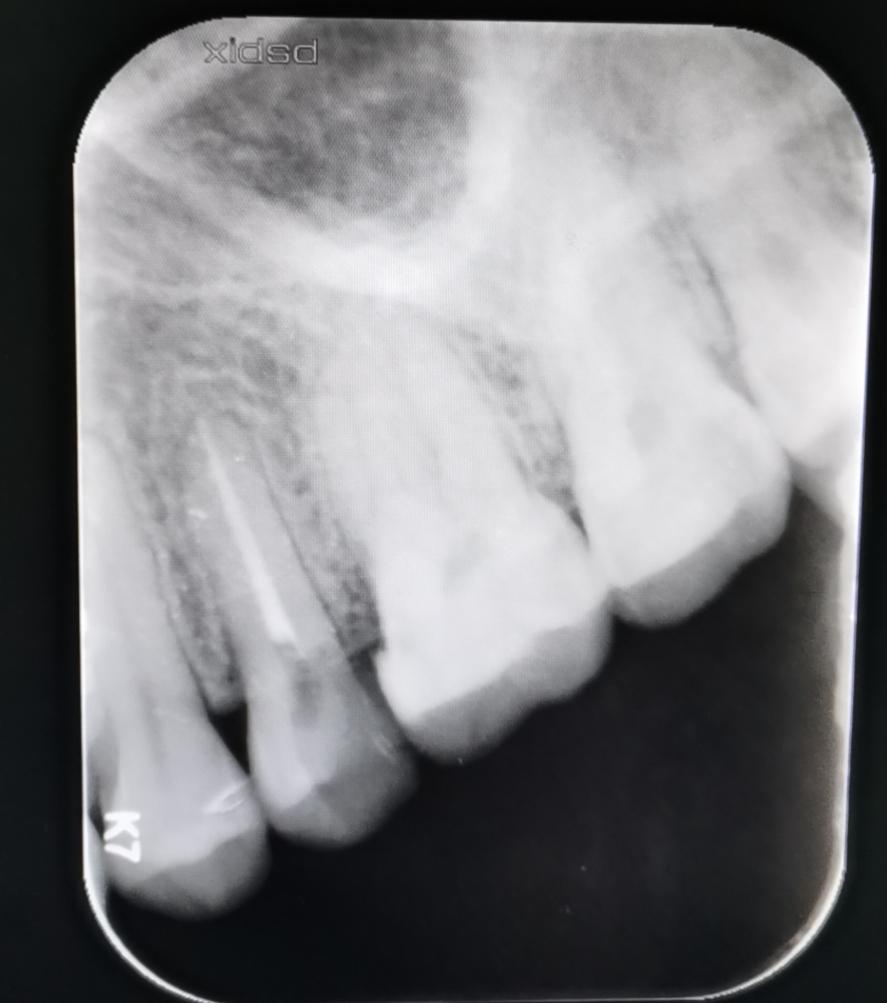

查看患者口腔情况,可见25中邻合面暂封物存在,无探痛,叩痛,牙齿无松动,牙龈缘轻度红肿,根尖区无红肿,冷测无反应,拍X线提示冠部低密度影近髓腔,根管内无填充物,根尖区无低密度影,诊断为25慢性牙髓炎(根管治疗中),26中龋。

结合患者治疗进度,决定予以25根管治疗+冠修复,26树脂充填修复。在去除25旧暂封物后,予以3%Naclo冲洗,并在根管显微镜下揭顶,探及1个根管口。根管口内探痛,拔髓不成形,手用K锉通畅根管,然后使用iRoot sp+热牙胶垂直加压填充,复拍X片提示恰填,予以GIC暂封。同时对26齿去腐净达牙本质浅层,比色后,给予流体树脂+3M P60树脂充填,抛光。

术前片

术后片